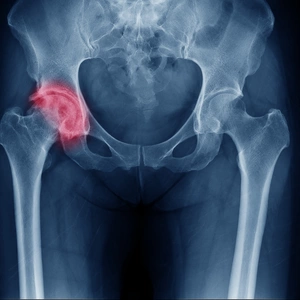

3D printing for personalised hip replacements

By using 3D printing technology, we can provide made-to-measure artificial joints that are surgical-grade and ideal for hip replacements.

Advanced imaging techniques capture the shape of a patient’s hip joint and its exact measurements. Computer software can then use this information to 3D print a replica of the hip joint, which is then used as a reference to position the new joint correctly during surgery.

An X-ray of a patients hip